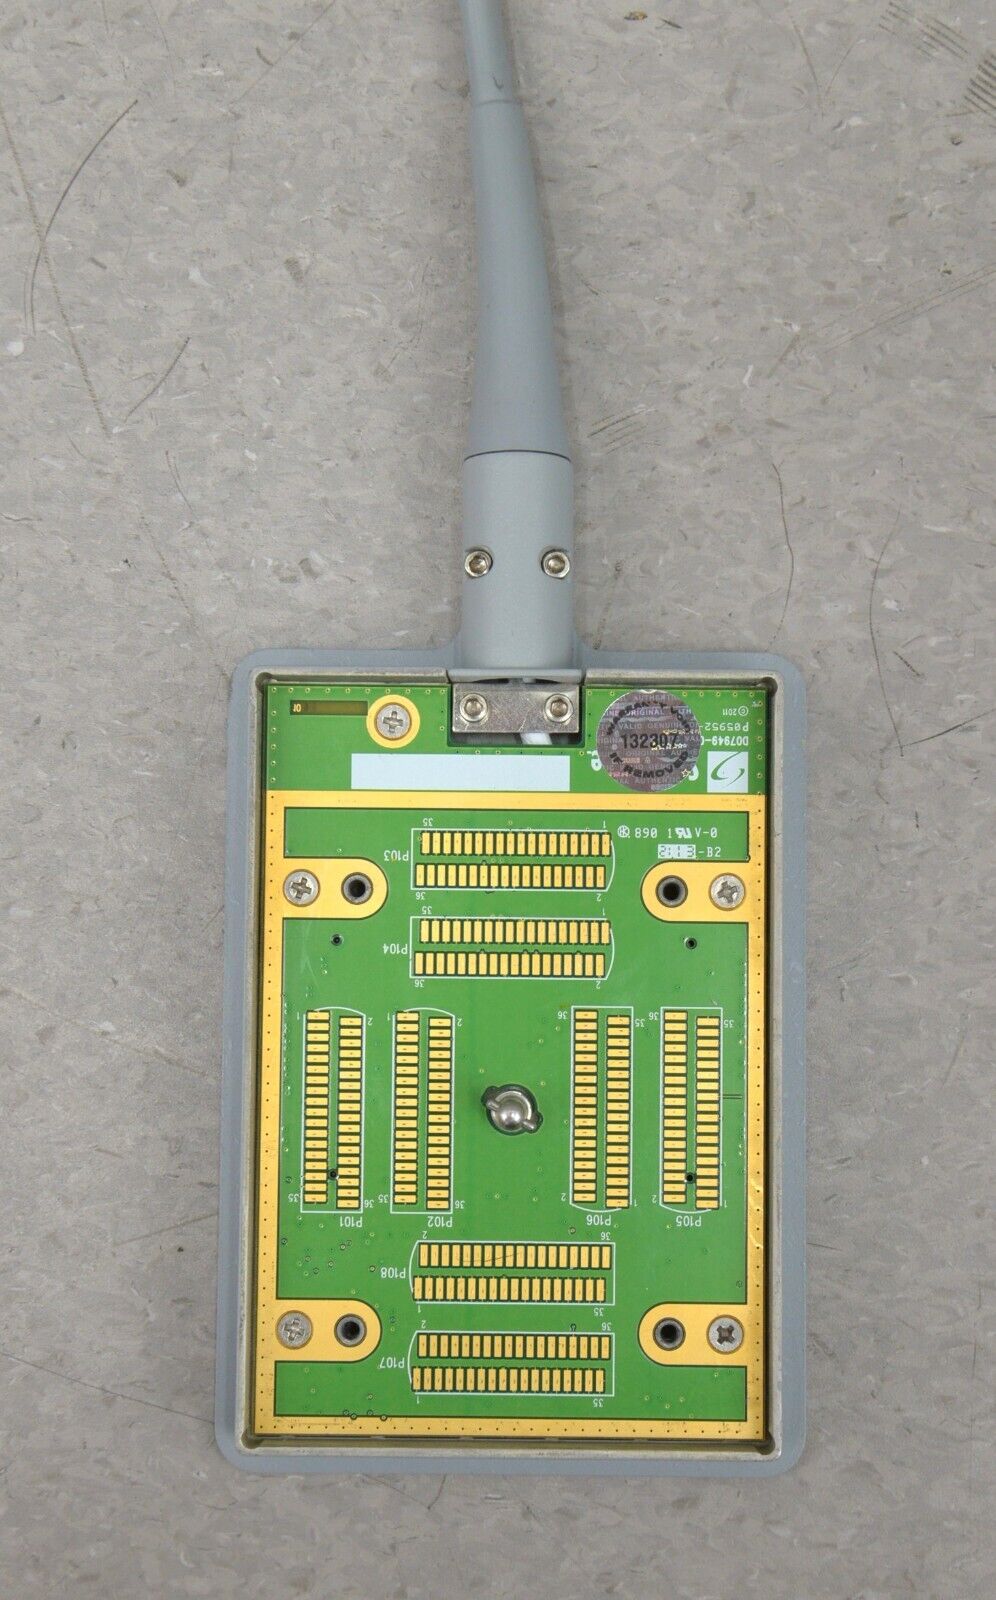

- Fujifilm Sonosite M-Turbo Ultrasound System W/ SonoSite P21x/5-1 MHz Transducer

January 15, 2025Fujifilm Sonosite M-Turbo Ultrasound System W/ SonoSite P21x/5-1 MHz Transducer

Fujifilm Sonosite M-Turbo Ultrasound System W/ SonoSite P21x/5-1 MHz Transducer

This Fujifilm Sonosite M-Turbo Ultrasound System W/ SonoSite P21x/5-1 MHz Transducer is in good working condition. This unit powers on properly and the display screen produces a clear picture. The buttons respond properly to selection and the connections are clean and in good condition. The battery holds a charge. There are a few minor scuff marks from previous use (see photos). This item comes with a 30 day satisfaction guarantee. Includes everything displayed in the photos and nothing else.